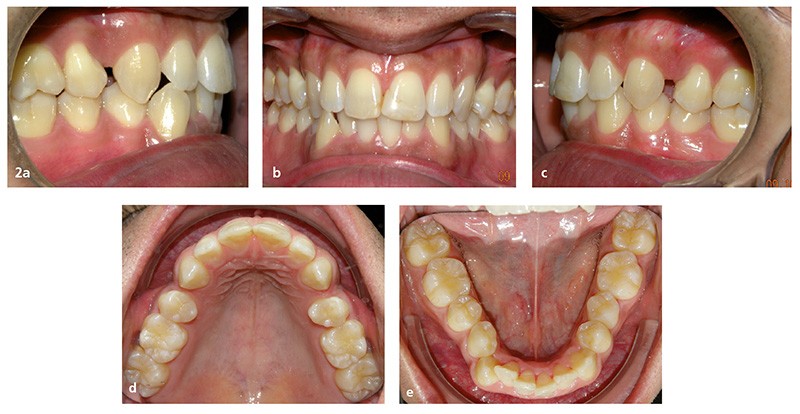

La demande du patient est d’aligner ses dents de l’arcade mandibulaire et de fermer les espaces résiduels d’extraction au maxillaire (fig. 2a à e). Ses fréquents déplacements professionnels à l’étranger, durant chaque fois plusieurs mois, ne lui permettent pas des rendez-vous réguliers au cabinet.

Sur le plan dentaire, dans le sens sagittal, il existe une classe II molaire thérapeutique et une classe I canine avec des espaces résiduels d’extractions en distal des canines chiffrés à 1,5 mm à droite et 2,5 mm à gauche. Les rebords des 11 et 21 ont été fracturés et reconstitués au composite (fig. 2a à e).

À la mandibule, la DDM est chiffrée à 4 mm environ ; 43 est en mésiovestibuloposition et en occlusion en bout à bout avec 12 ; 42 est en linguoposition, 35 en rotation axiale mésiolinguale ; 44 présente une anomalie de forme avec un diamètre mésiodistal augmenté et vestibulolingual diminué (dysharmonie dento-dentaire).